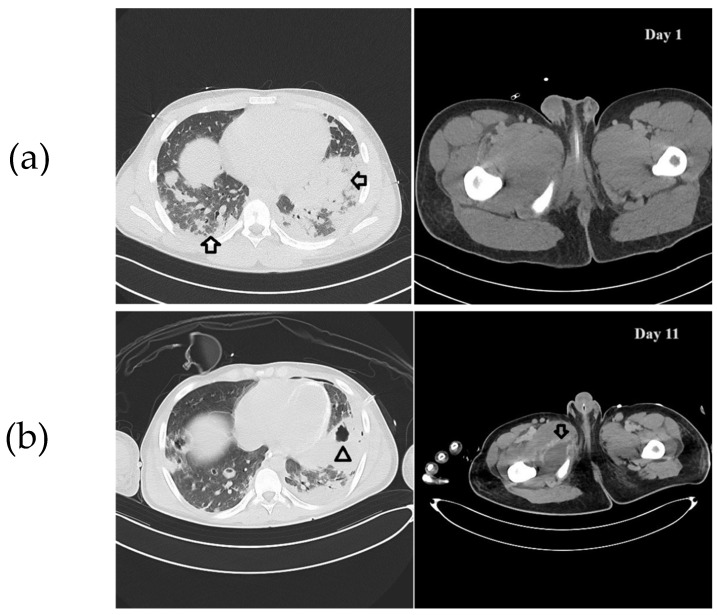

Background: Methicillin-resistant Staphylococcus aureus (MRSA) is a significant cause of healthcare-associated infections in Europe. It has become increasingly prevalent in community settings, causing skin and soft tissue infections (SSTIs). Managing community-acquired (CA) MRSA infections is challenging due to its high virulence and resistance to common antibiotics, and prevention outside the hospital setting is complex. Combination therapy has demonstrated efficacy in the treatment of severe MRSA infections. Furthermore, surgical source control is critical in treating CA-MRSA infections, involving removing the primary infection site to interrupt bacterial replication. Timeliness and a correct surgical approach are essential for successful treatment outcomes and improved quality of life. Methods: This report details the case of a 15-year-old athlete who was admitted to the intensive care unit with septic shock caused by CA-MRSA. Results: Despite initial treatment, his condition rapidly worsened. A computed tomography (CT) scan identified multiple abscesses (in the lungs, limbs, thyroid, and subscapular region) along with other complications. To achieve adequate tissue concentrations at all affected sites, a triple-targeted antimicrobial therapy was initiated and adjusted based on therapeutic drug monitoring (TDM). At the same time, daily surgical debridement was performed. The patient responded significantly to this treatment, and blood cultures eventually returned negative. Conclusions: A multidisciplinary approach involving early source control, tailored antimicrobial therapy, and, if monotherapy fails to control infection, combination therapy is advisable to treat life-threatening CA-MRSA infections.